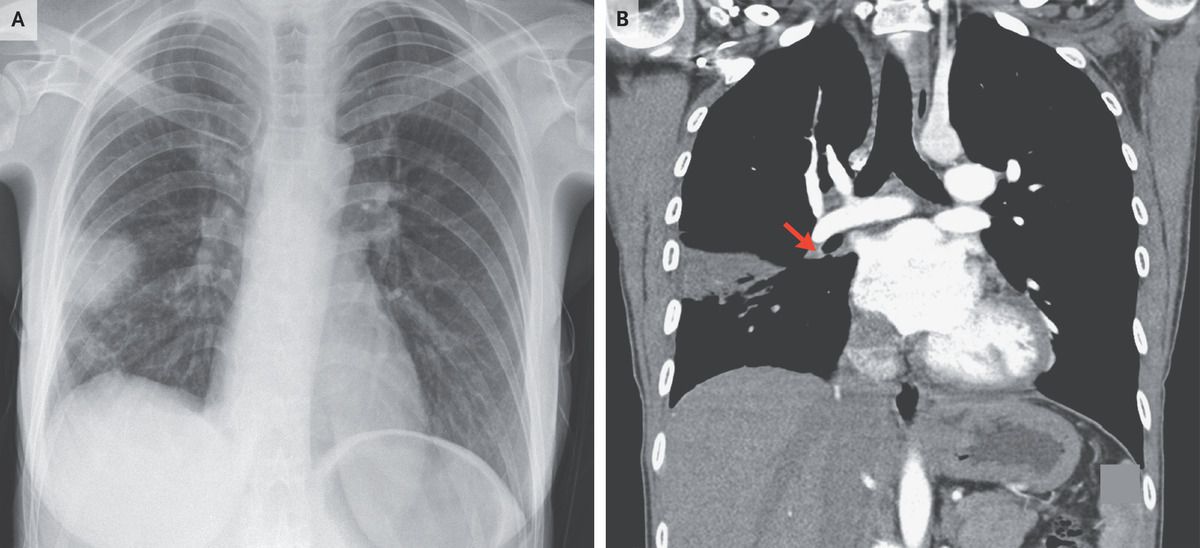

A 28-year-old woman presented to the emergency department with a 3-day history of dry cough and pleuritic chest pain. She had a history of ulcerative colitis and pulmonary embolism. Her heart rate was 87 beats per minute and her oxygen saturation 99% while she was breathing ambient air. On physical examination, fine crackles could be heard in the right lower lung. The legs were symmetric. Levels of troponin, d-dimer, and N-terminal pro–B-type natriuretic peptide were normal. An electrocardiogram showed deep S waves in lead I and T-wave inversions in lead III. A chest radiograph showed a dome-shaped, pleural-based opacity in the right lung (Panel A), consistent with Hampton’s hump, a finding that aroused concern about recurrent pulmonary embolism, even though her vital signs and results on laboratory testing were normal. Computed tomographic pulmonary angiography revealed filling defects in the right lower lobar pulmonary artery (Panel B, arrow) and its segmental branches as well as a peripheral wedge-shaped consolidation, confirming a diagnosis of pulmonary embolism with distal pulmonary infarction. Hampton’s hump, a radiographic sign of pulmonary infarction, is a rare finding in patients with pulmonary embolism. The patient started anticoagulation therapy, with a plan for lifelong therapy, and her symptoms resolved.